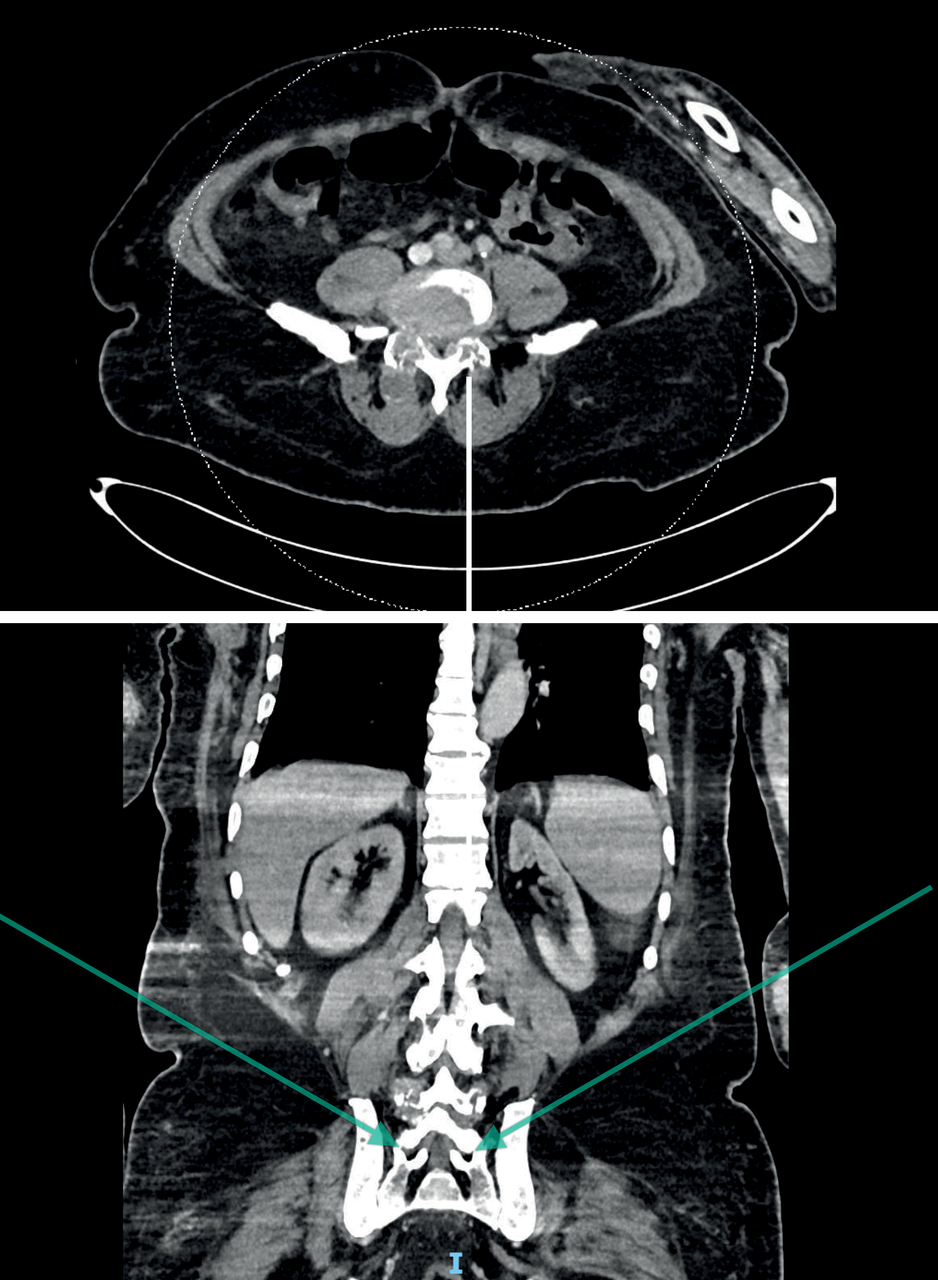

Le scanner montre :

• un rétrécissement canalaire serré en C4-C5 et L4-L5 ;

• des dépôts microcristallins diffus d’urate de sodium, notamment au sein des articulations apophysaires postérieures ;

• une arthrite interapophysaire postérieure bilatérale L4-L5 avec collection des parties molles et remaniements inflammatoires, dont l’aspect est évocateur d’un accès goutteux.